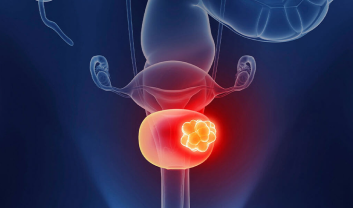

Testicular cancer, a condition that may sound daunting, is a topic that requires our attention . Dr. Prabhat Ranjan, a distinguished...